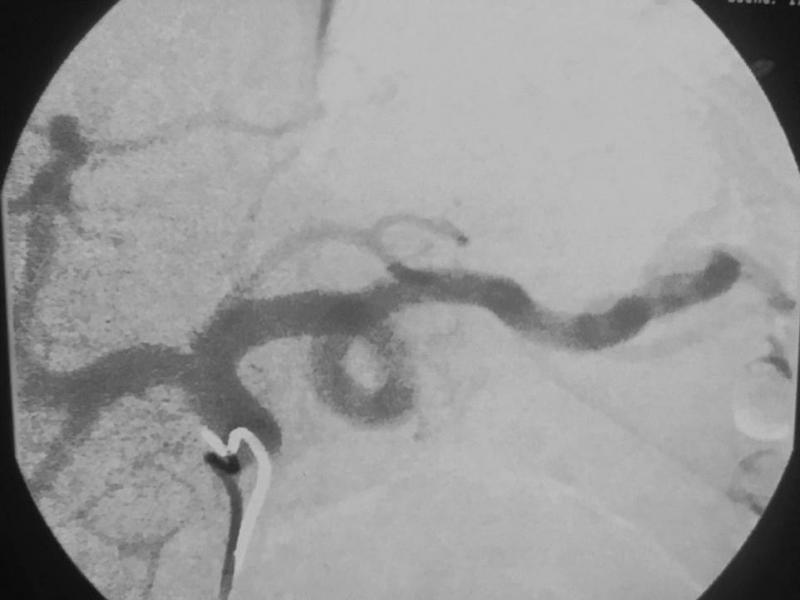

In order to suppress production of ghrelin, interventional radiologists embolize the gastric artery, the main artery that supplies blood to the stomach. Embolization is performed by injecting microscopic beads into the bloodstream. The beads make their way to the artery, where they block the smaller vessels. This is all accomplished through a minimally invasive, non-surgical technique through a small catheter inserted in the wrist or groin.

The initial patient in the study represented the first use of left gastric artery embolization in the Western Hemisphere to treat morbid obesity. All the patients were treated on an outpatient basis. The researchers followed a strict protocol, monitoring the patients' quality of life and taking blood samples to ensure the patients' well-being.

While previous embolizations used the groin for access, Syed was the first to introduce the embolic agents through the radial artery in the wrist—a safer, more convenient access site in the obese population.